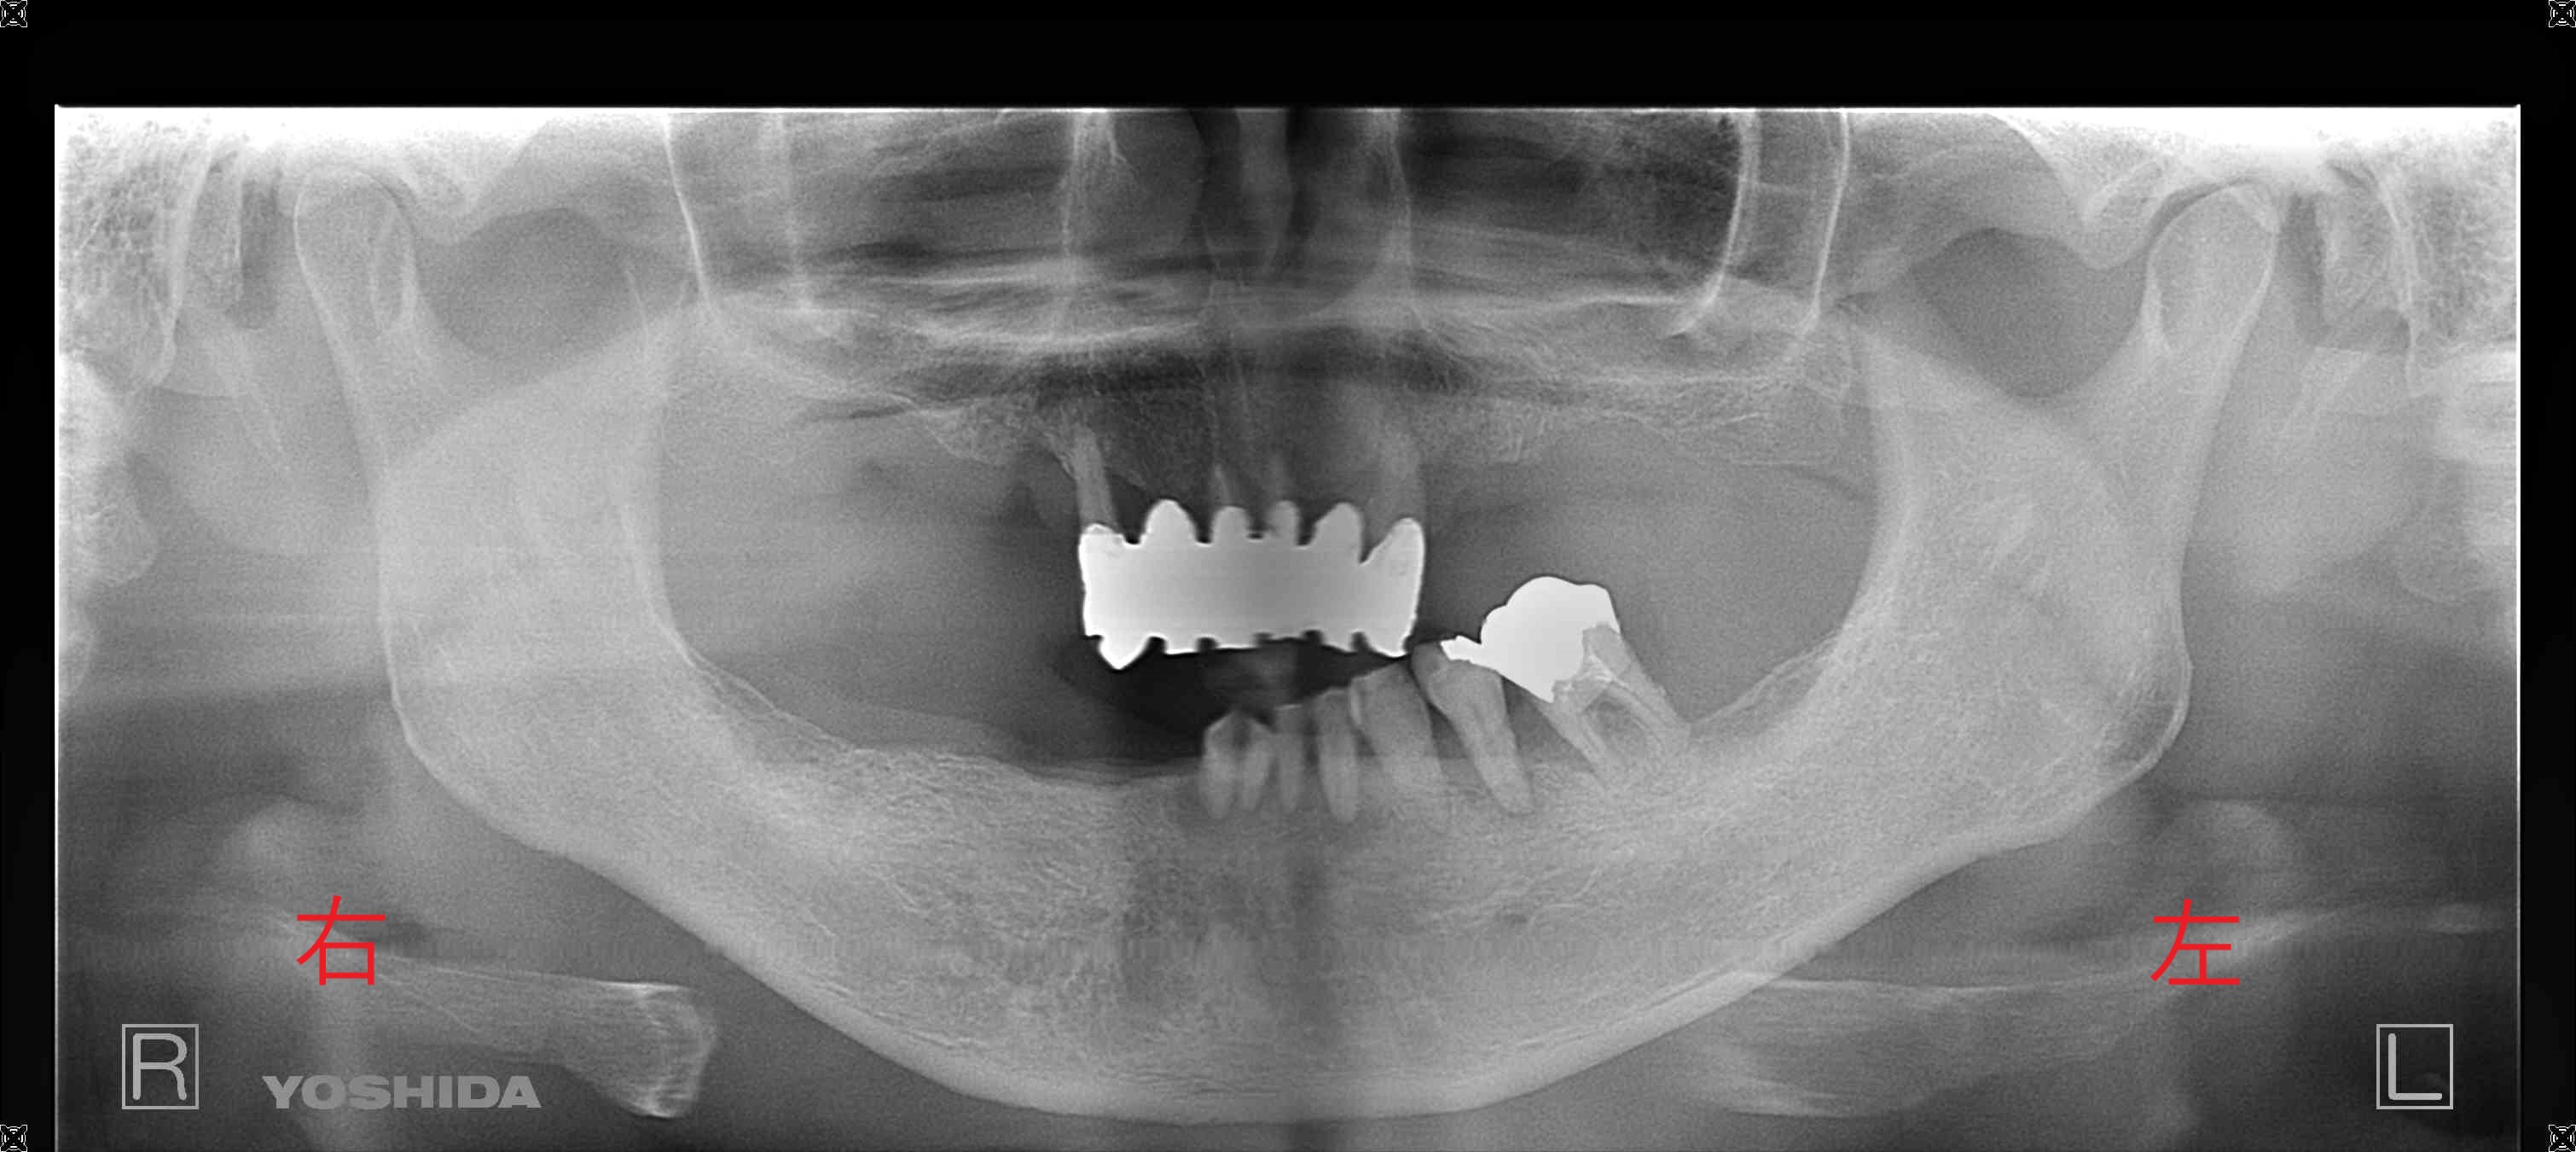

レントゲン写真からも重度の歯周病が確認され、抜歯が必要な状態であることがわかります。こうした場合、歯科医師としても歯を残せないことに無力感を覚える場面です。